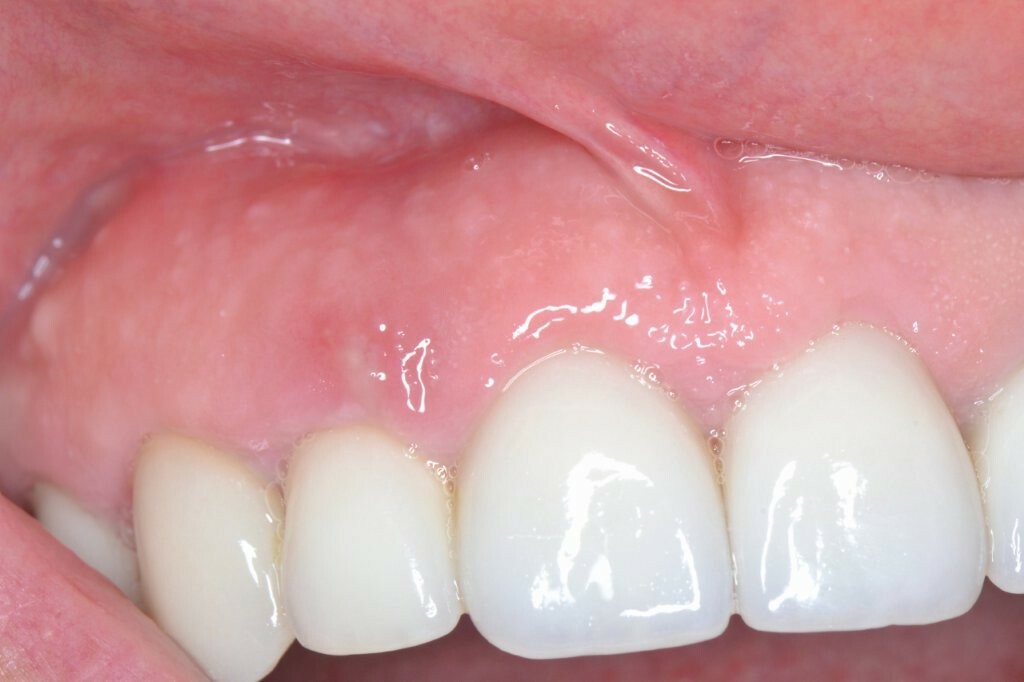

Wir behandelten in unserer Praxis einen Patienten, der über Schmerzen klagte, die durch eine Abszessbildung in Implantatregion 12 verursacht wurden. Das Implantat war ein Jahr zuvor von seinem Allgemeinzahnarzt inseriert worden.

Klinisch und radiologisch zeigte sich eine Entzündung mit Schwellung des Weichgewebes und Pusabsonderung auf Druck. Die Taschentiefe betrug 5-6 mm, der periimplantäre Knochenverlust betrug 3 mm.

Es wurde eine Periimplantitis diagnostiziert und eine Behandlung empfohlen.